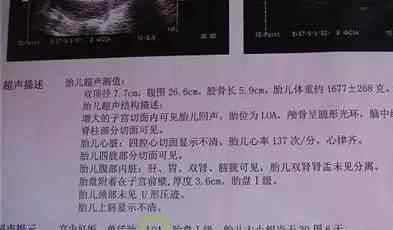

b超单子上那些关于胎位的术语

◆胎位loa是什么意思?

b超检查,其中报告有胎位loa,是什么意思?很多妈妈都不太了解。作为一个孕妇,有一半的专家告诉你,LOA指的是左枕前位。也就是说可以自然交付。这个问题我们再详细说说。

胎位的书写表现在三个方面:

代表骨骼在骨盆左侧或右侧,缩写为左(L)或右(R);

它代表骨骼的名称,如“枕”(“O”),“骶骨”(“S”),“下巴”(“M”),“肩”(“Sc”)。

意思是骨头在骨盆的前面、后面或对面。比如枕骨在骨盆左侧,面向前方,胎位就是左枕前(LOA),这是最常见的胎位。

◆每个胎位的缩写如下:

顶骨暴露有六种胎位:LOA、LOT、ROA、ROT和ROP

臀大肌有六种胎位:LSA、LST、LSP、RSA、RST和RSP

面部表情有六种胎位:左前颏(LMA)、左外颏、右前颏、右外颏和右后颏

露肩有四种胎位:左前肩、左后肩、右前肩和右后肩